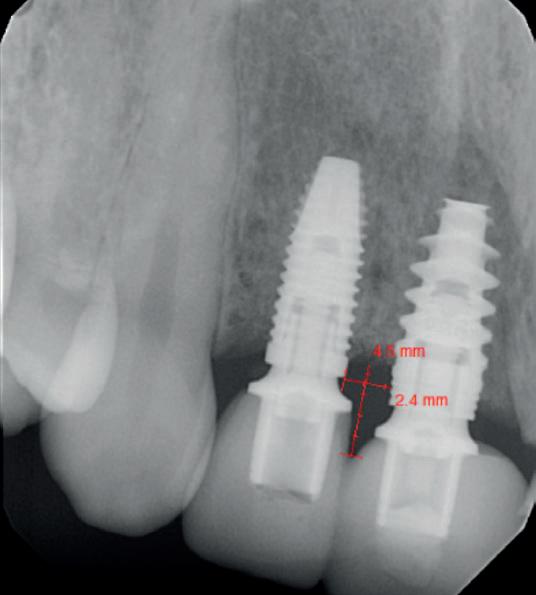

De asemenea, trebuie evaluate anual modificările radiografice. În ședința de inserție a restaurării, se înregistrează o radiografie bitewing standardizată pentru a permite evaluarea anuală a modificărilor osoase din jurul implantului. Remodelarea osului alveolar în primul an este bine documentată și depinde de tipul de implant utilizat; cu toate acestea, nu ar trebui să apară apical de primul filet al implantului. Prin urmare, este importantă abilitatea de a vizualiza filetele implantului pe radiografii. Modificările pierderii osoase de 2 mm sau mai mult după primul an reprezintă un semn de periimplantită. De îndată ce pierderea osoasă este recunoscută, pacientului trebuie să i se recomande terapia imediată pentru a opri procesul de boală.

Utilizarea platform-switch și-a dovedit eficiența în sistemele moderne de implanturi. Însă acum, zona conică inversată oferă mai mult spațiu și un suport mai bun de aderență pentru țesutul dur și moale decât formele cilindrice ale implanturilor, așa cum cum se poate vedea în imaginea următoare.

Suprafața microstructurată din zona conică inversată sprijină atașarea osului și a țesutului conjunctiv. Atunci când marginea acesteia este poziționată subcrestal, este recomandată utilizarea unui material de augmentare (xenogrefă sau os autolog) care poate preveni dezvoltarea țesutului moale în zona conică inversată și poate oferi suport pentru o mai bună osteointegrare.